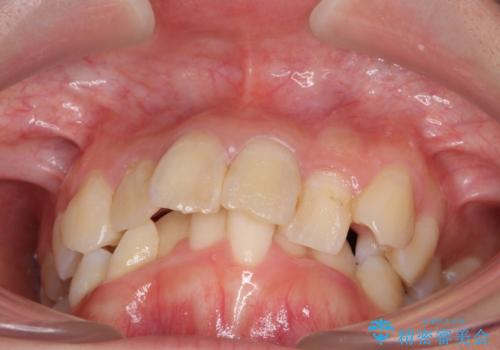

- 内側に倒れ込んだ歯や下の前歯が隠れてしまうほどの咬み合わせを改善したいとのことで来院された患者様です。

下顎の叢生を解消するために抜歯が必要であり、奥歯の咬み合わせや口元の印象から、上顎も同様に抜歯と判断し、上下左右の第1小臼歯4本抜歯してワイヤー装置にて矯正治療を行うこととしました。